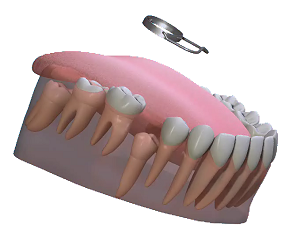

• Hàm giữ khoảng là một khí cụ tháo lắp hoặc cố định nhằm để giữ khoảng cần thiết cho răng vĩnh viễn mọc.

Có 2 loại chính đó là hàm giữ khoảng tháo lắp và giữ khoảng cố định. Lựa chọn hàm giữ khoảng phụ thuộc vào từng trường hợp lâm sàng cụ thể, sự hợp tác và điều kiện vệ sinh của trẻ, điều kiện tài chính của gia đình. Dù là hàm giữ khoảng tháo lắp hay cố định thì nó phải bảo đảm được chức năng ăn nhai, giữ được kích thước dọc và ngang, bảo tồn được chức năng phát âm và thẩm mỹ, tương hợp với mô mềm, cho phép vệ sinh tốt, chịu lực và dễ sử dụng.